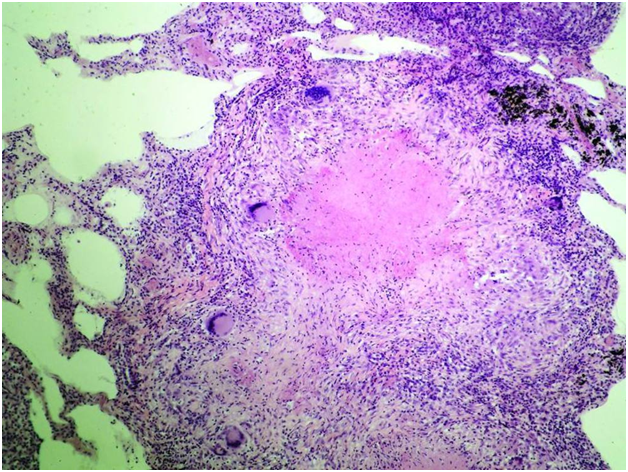

Микроскопический взгляд на мишитарный туберкулез легкого: фотодокументация

Раздел: Снимки-откровения